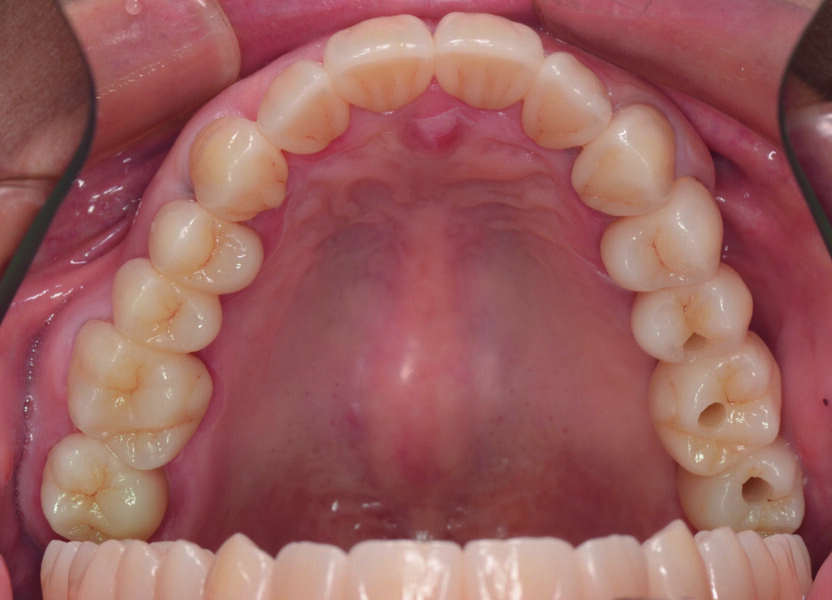

Fig. 10a : Résultat hautement esthétique et fonctionnel.

Fig. 10b : Résultat hautement esthétique et fonctionnel.

L’aspect fonctionnel est une partie importante de ma tâche journalière au laboratoire, et la combinaison du traitement virtuel de la fonction avec des matériaux efficaces, qui facilite considérablement mon travail, me donne entière satisfaction. À mon avis, la zircone, et en particulier Zolid FX Multilayer, est idéale, car elle allie esthétique et résistance (Figs. 10a et b). Toutefois, la zircone présente aussi des inconvénients ; par exemple, des contraintes inadéquates sur la couronne sont susceptibles d’entraîner une parodontite ou des problèmes condyliens, ou encore des difficultés de préparation. C’est pourquoi, dans notre travail de prothésiste dentaire, nous devons tenir compte à la fois de l’occlusion et de la fonction.